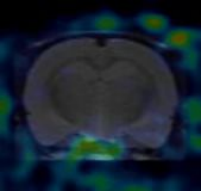

4.實驗動物(wù)的(de)靶器(qì)官及全身(shēn)顯像或模拟臨床功能(néng)測定試驗的(de)研究方法,試驗條件(jiàn)等資料,試驗觀察各時(shí)相(xiànεg)的(de)顯像或功能(néng)測定結果

一(yī)、實驗動物(wù)的(de)全身(shēn)顯像及延遲顯像

實驗動物(wù)為(wèi)小(xiǎo)鼠1隻,由杭州醫(yī)學院提供,體(tǐ)重約200g,雄性,。注射藥物(wù)後麻醉後進行(xíng)PET掃描,采←集圖像,獲得(de)藥物(wù)在體(tǐ)內(nèi)分(fēn)布圖。顯像後實驗動物(wù)逐漸蘇醒,恢複正常,飲食、二便、精神狀态佳。

PET/CT采集:需在注射顯像劑後50min準時(shí)進行(xíng)掃描。靜(jìng)态掃描時(shí)間✘(jiān)是(shì)注射後50 min,采集20分(fēn)鐘(zhōng)。動态采集時(shí)間(jiān)為(wèi)0-60分(fēn)鐘(zhōng)。CΩT和(hé)PET采集參數(shù)和(hé)重建方法需同腦(nǎo)18F-FDG 顯像一(yī)緻。掃描組需嚴格控制(zhì)注射時(shí)間(jiān)及掃描時(shí)¶間(jiān),并嚴格記錄掃描時(shí)間(jiān)。